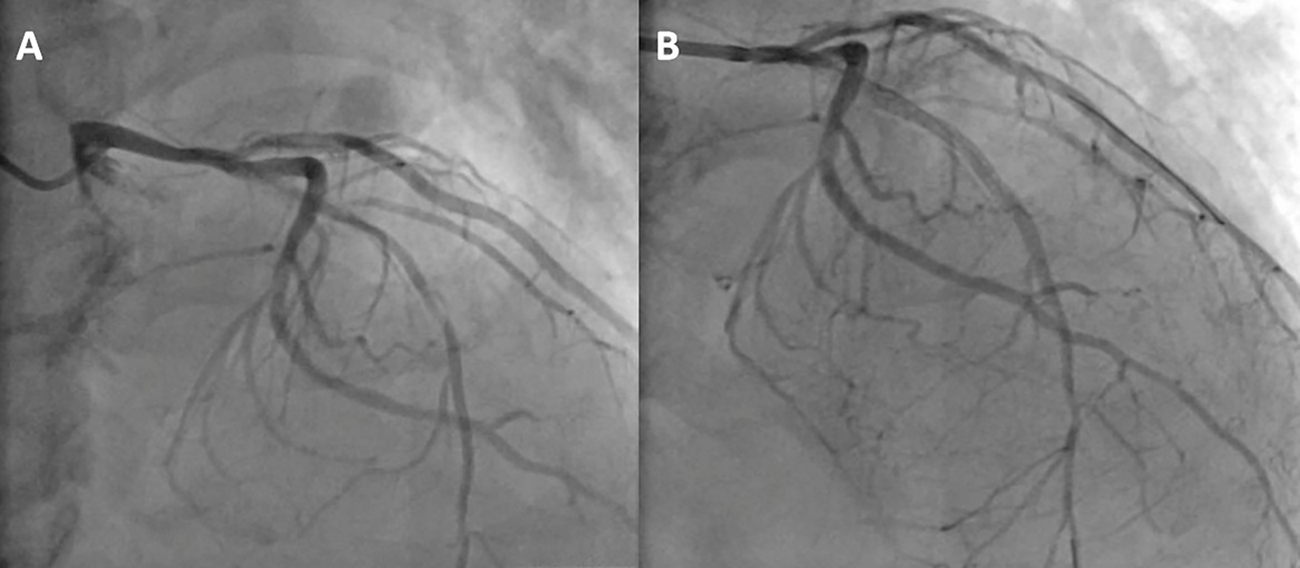

On June 8, 2024, right radial artery access was obtained under local anesthesia with 1% lidocaine. Coronary angiography (CAG) revealed 90% diffuse stenosis in the proximal left anterior descending (LAD) artery and 70% segmental stenosis in the Diagonal Branches(D) (Figure 2A). Intravascular ultrasound (IVUS) revealed severe calcified lesions in the proximal LAD. A shockwave balloon (3.0 × 12 mm) was deployed in the proximal LAD, delivering 80 pulses, followed by the implantation of three drug-eluting stents (2.5 mm × 33 mm, 2.75 mm × 26 mm, and 3.0 mm × 15 mm). IVUS assessment confirmed good stent apposition, with a minimal stent area (MSA) greater than 6.0 mm² (Figure 2B).

Figure 2

(A) CAG indicating a 90% diffuse stenosis in the proximal segment of the LAD artery. (B) the LAD artery after stent implantation).